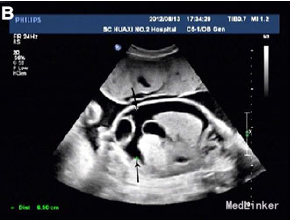

31岁女性,G2P1,孕31周,因高血压、少尿、胎儿和胎盘水肿就诊

实验室检查提示Hb 80g/L,极低的血清铁蛋白 超声提示严重腹水、心肌肥大、心包积水,羊水过多,但无皮肤水肿 轻微胸腔积水 病毒感染检查提示均为阴性 初步诊断为子痫前期、胎儿水肿和缺铁性贫血 孕妇外周血压114-138/67-92 口服降压药,注射地塞米松 入院4天出现咳嗽,不伴干湿罗音,四肢水肿加重,血压升到142-165/95-100,Hb 72g/L

孕31+4周时诱发生产 第二产程时,出现严重的呼吸困难和血压升高(177/120) 给予呋塞米静注 可见婴儿头部,故继续阴道分娩,助产 产下一男婴2200g,Apgar评分分别为2,2 胎盘巨大,重1250g 新生儿22min后死亡 尸检提示心肺衰竭死亡 最后诊断为镜像综合征